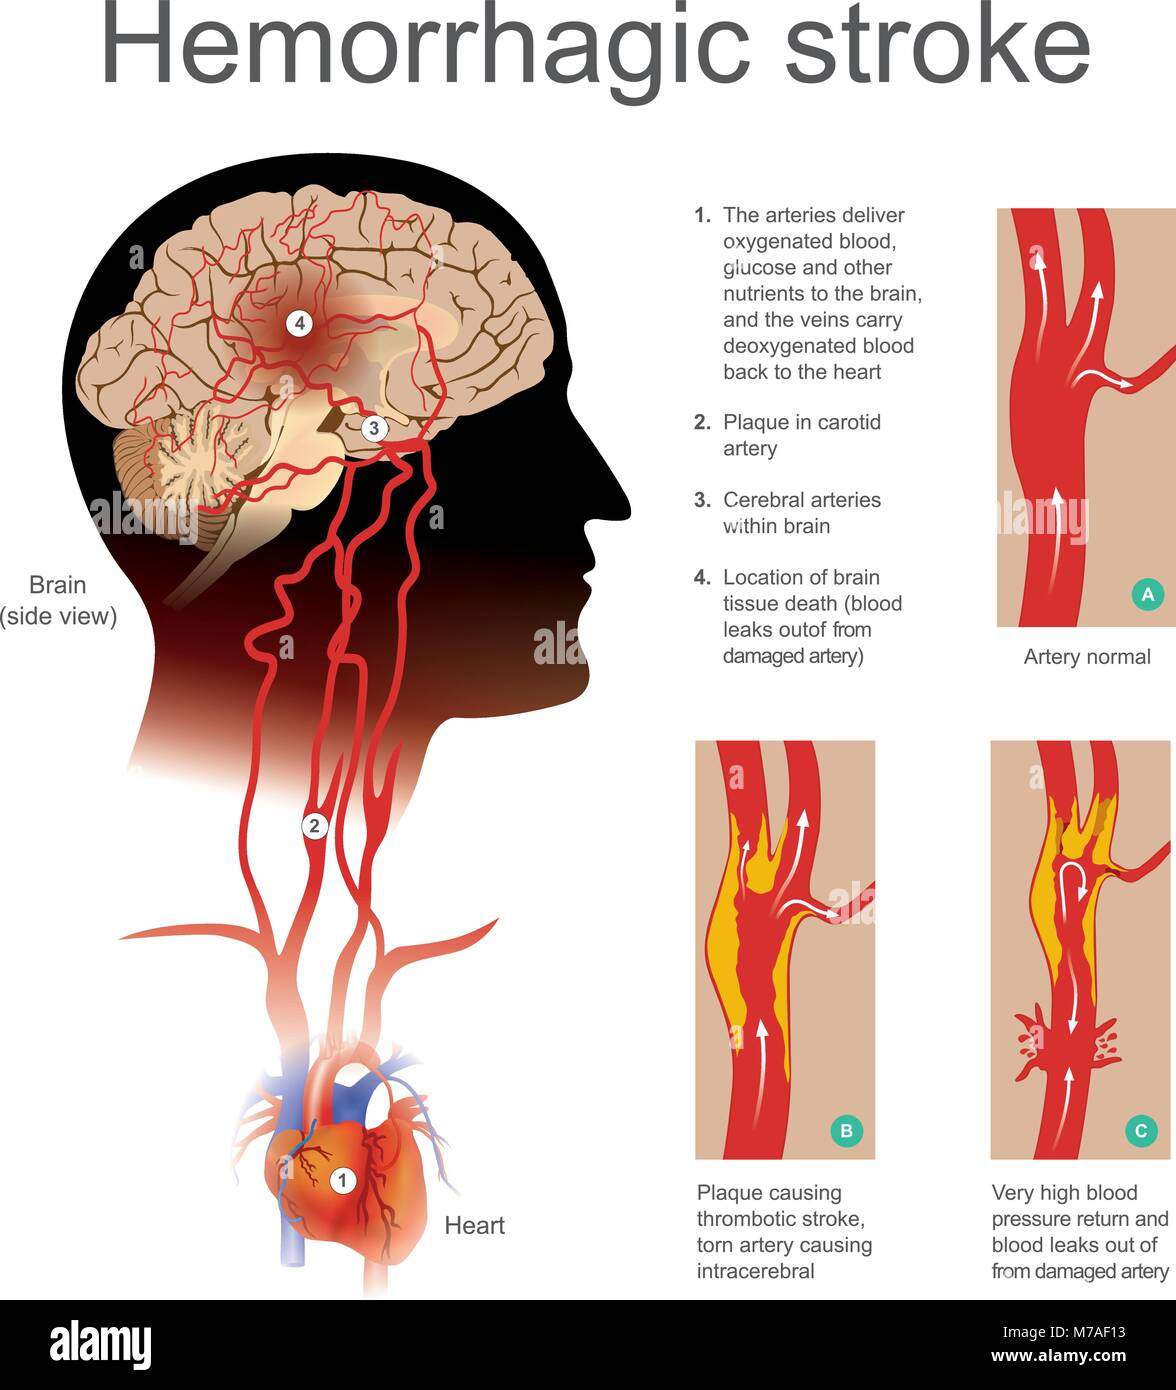

La placca causando ictus trombotico arteria strappata causando intracerebrale. Molto elevato ritorno di sangue e perdite di sangue fuori dalla arteria danneggiata. Illustrazione hu Illustrazione Vettorialehttps://www.alamy.it/image-license-details/?v=1https://www.alamy.it/foto-immagine-la-placca-causando-ictus-trombotico-arteria-strappata-causando-intracerebrale-molto-elevato-ritorno-di-sangue-e-perdite-di-sangue-fuori-dalla-arteria-danneggiata-illustrazione-hu-176637583.html

La placca causando ictus trombotico arteria strappata causando intracerebrale. Molto elevato ritorno di sangue e perdite di sangue fuori dalla arteria danneggiata. Illustrazione hu Illustrazione Vettorialehttps://www.alamy.it/image-license-details/?v=1https://www.alamy.it/foto-immagine-la-placca-causando-ictus-trombotico-arteria-strappata-causando-intracerebrale-molto-elevato-ritorno-di-sangue-e-perdite-di-sangue-fuori-dalla-arteria-danneggiata-illustrazione-hu-176637583.htmlRFM7AF13–La placca causando ictus trombotico arteria strappata causando intracerebrale. Molto elevato ritorno di sangue e perdite di sangue fuori dalla arteria danneggiata. Illustrazione hu